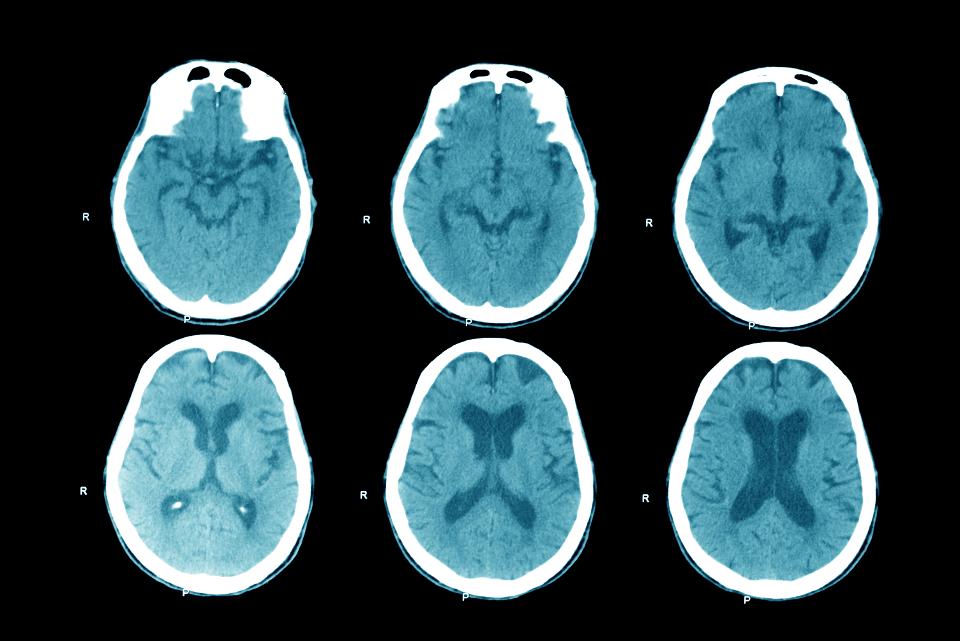

Investigating what part of the brain was damaged based on behavior. Hearing some great conversations! #psych #collaboration #brainfunctions

Upcoming Video - Cerebral Anemia #cerebralanemia #bloodflow #brainfunctions #cerebral #brainhealth #cerebralanaemia #cerebralischemia youtube.com/shorts/nOOL9aR…

Upcoming Video - Cerebral Anemia #cerebralanemia #bloodflow #brainf...